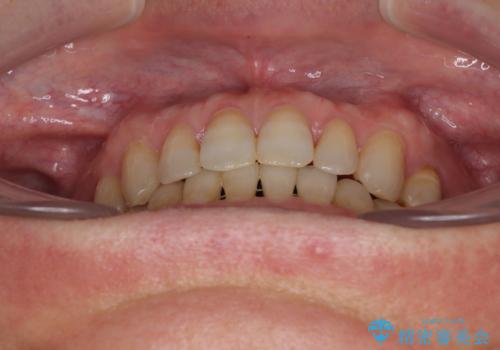

- 前歯のデコボコと隙間の空いた歯列を気にして来院された患者様です。

下顎前歯が隠れるほどのディープバイトにより、強い咬合力と突き上げで上顎歯列に隙間が空いている状態でした。

手前に傾斜している奥歯をワイヤー装置で立ち上がらせ、咬み合わせの高さを挙上することで突き上げを解消し、空隙歯列を改善していくこととしました。

ディープバイトが改善され、睡眠時の食いしばりも緩和され、顎への負担が軽減されました。